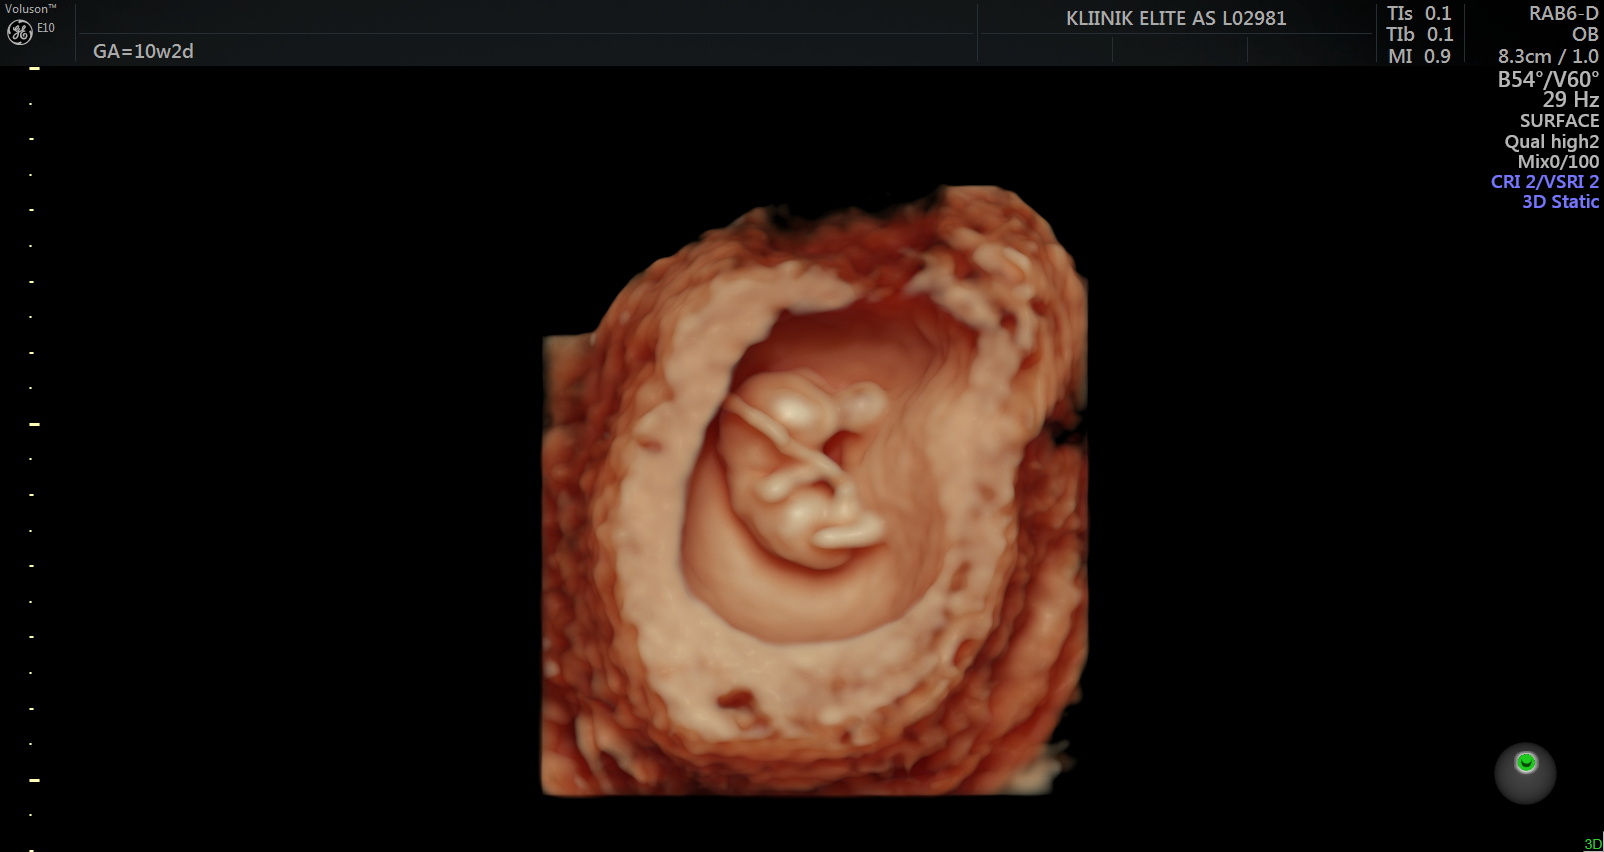

Loode:

Ultraheliuuringul on loode nähtav. Hakkab moodustuma loote selgroog ning ajul on moodustunud kaks sagarat. Lootel hakkavad arenema käed, jalad ja nägu. 8. nädalal on lootel moodustunud kõik peamised siseorganid. Süda lööb korrapäraselt. Loode on umbes 4 sentimeetrit pikk. Kuni 14.

nädalani mõõdetakse lapse pikkust peast seljani (CLR).

Uuringud:

Rasedust saab tuvastada koduse rasedustestiga. Emakaõõnes saab rasedust diagnoosida 6. rasedusnädala alguses (5+). 6.-7. rasedusnädalal saab ultraheliuuringu abil tuvastada loote südametöö ja välistada emakaväline ja peetunud raseduse. Varajane ultraheli (6.-7. nädalal) on oluline ka embrüo väärarengute diagnostikas. Esimesel visiidil teostatakse järgmised analüüsid – vereanalüüs, analüüsid suguteedest, uriiniproov.

Loote sõrmed ja varbad on sel ajal eristatavad. Pea moodustab peaaegu poole loote suurusest. Võrreldes 7. nädalaga on 10. nädalal loote kaal kahekordistunud. Kujunema hakkavad sõrme- ja varbaküüned. 11. nädalaks on moodustunud loote munandid või munasarjad. Loode suudab avada suud ning keel on välja arenenud. Välised suguelundid on nähtavad, kuid ultraheliuuringu käigus on neid veel keeruline eristada. Sel perioodil saab soo tuvastada Panorama ja Nifty testiga. 12. nädalal on lootel silmalaud. Loode liigub emakas ringi, kuid naine seda ei tunne. 12. nädalal kaalub loode umbes 25 grammi ja tema jala pikkus on 1 sentimeeter. Loode võib neelata väikestes kogustes lootevedelikku. 13.

nädalaks on lootel olemas kõik luud.